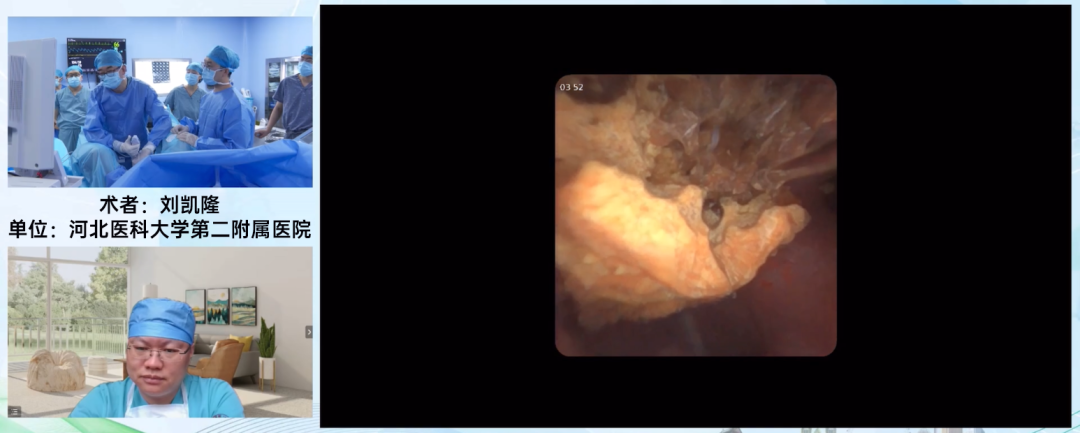

河北医科大学第二医院 刘凯隆教授

刘凯隆教授使用普生7.5Fr一次性输尿管软镜PU3033A为63岁男性患者进行输尿管软镜碎石术。该患者合并强直性脊柱炎,导致体位受限。

患者于术前已置入支架两周,但下段输尿管仍较为狭窄,只能置入10/12Fr的鞘。普生7.5Fr细镜可完美搭配细鞘,术中操控性能优异,手术安全顺利地进行,术后探查无残石,清石效率非常高。